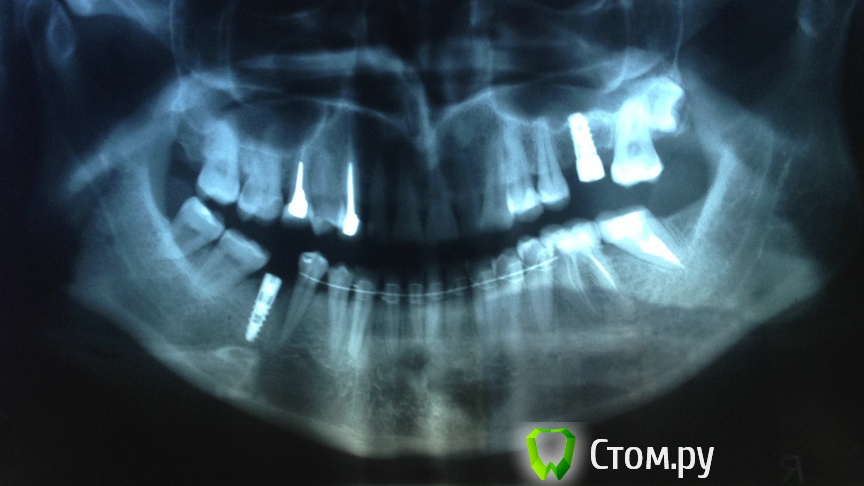

Nnn Опубликовано 23 апреля, 2014 Автор Поделиться Опубликовано 23 апреля, 2014 (изменено) На всякий случай снимки. Я писала про один имплант в своем вопросе, но на самом деле у меня два импланта, еще вверху один тоже на корневом зубе. Там тот же вопрос с коронкой Изменено 23 апреля, 2014 пользователем Nnn Ссылка на комментарий